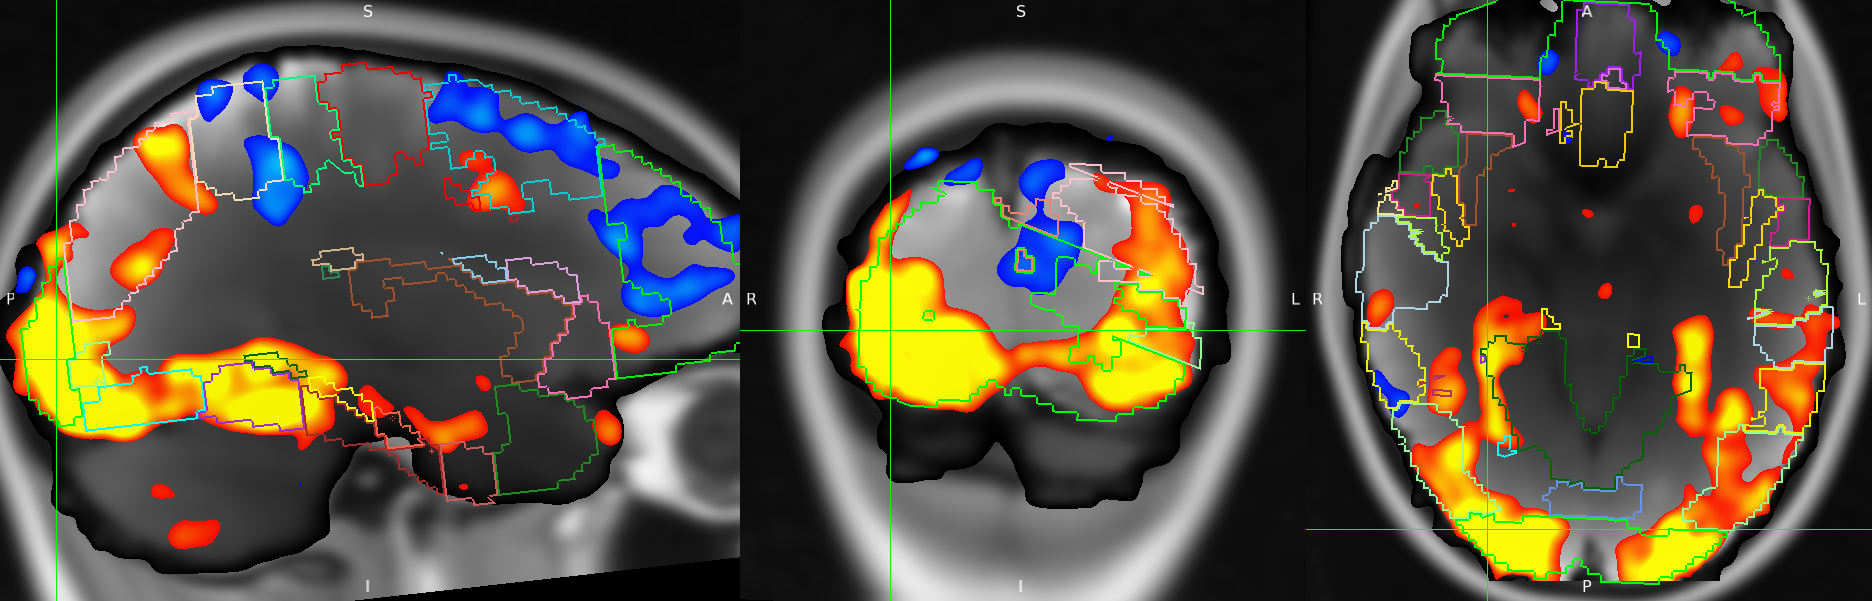

Remember that we are actually performing this process on the data for every single voxel in our dataset. This means that we will end up with an entire 3D image of t-statistics and another 3D image of p-values. We often present the results of an fMRI analysis with images that look like this:

What we are looking at here are a handful of 2D slices of our 3D dataset, with the fMRI data (averaged across time) shown in the background in grey, and the t-statistic values shown through red (low) to yellow (high). We are only displaying t-statistics that were statistically significant, i.e. all of the voxels where the t-statistic (and the corresponding p-value) was too low are not displayed.

This will bring up a FSLeyes window that looks something like this:

The table on the right (the cluster browser) allows you to explore your results in more detail.

Use the drop-down menu to select the test (a.k.a. COPE) that you are interested in. Then press the Add Z-statistics button to open the Z-statistic image for that test.

Now press the little → button in the first row, underneath the Z Max location column. This tells FSLeyes to display the location of the maximum Z-statistic for your test (i.e. the locatoin of the best model fit).

Now we can see exactly where the brain was responding to our stimulus (or, if we are comparing two stimuli, where the brain responded more strongly to one stimulus when compared to the other stimulus).

But you might want some more detailed information as to which anatomical regions were involved in your experiment. We can explore our results a little further by using an anatomical atlas, which is an image that contains anatomical labels for every voxel in the brain.